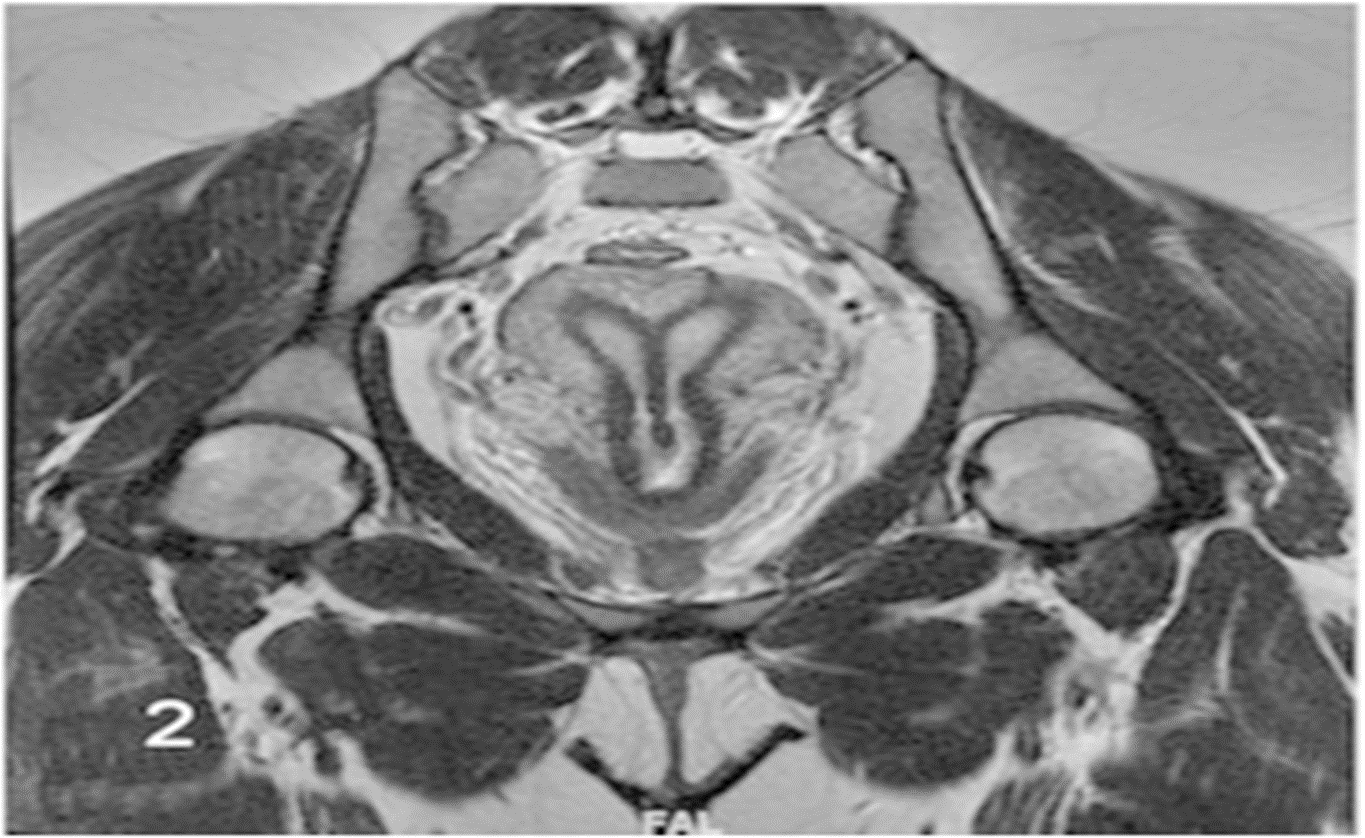

(2) MRI; T-2 weighted; coronal plane: septate uterus